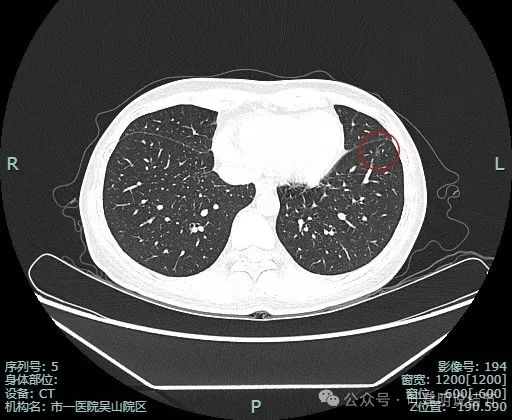

薄层影像:

病灶离叶间裂较近,几乎贴着,叶间胸膜略有牵拉向病灶侧,但力量小。可见有一细小血管走向病灶。

他处也有小血管进入,整体轮廓与边界清。

边缘显得毛糙。

边缘区也是磨玻璃密度。